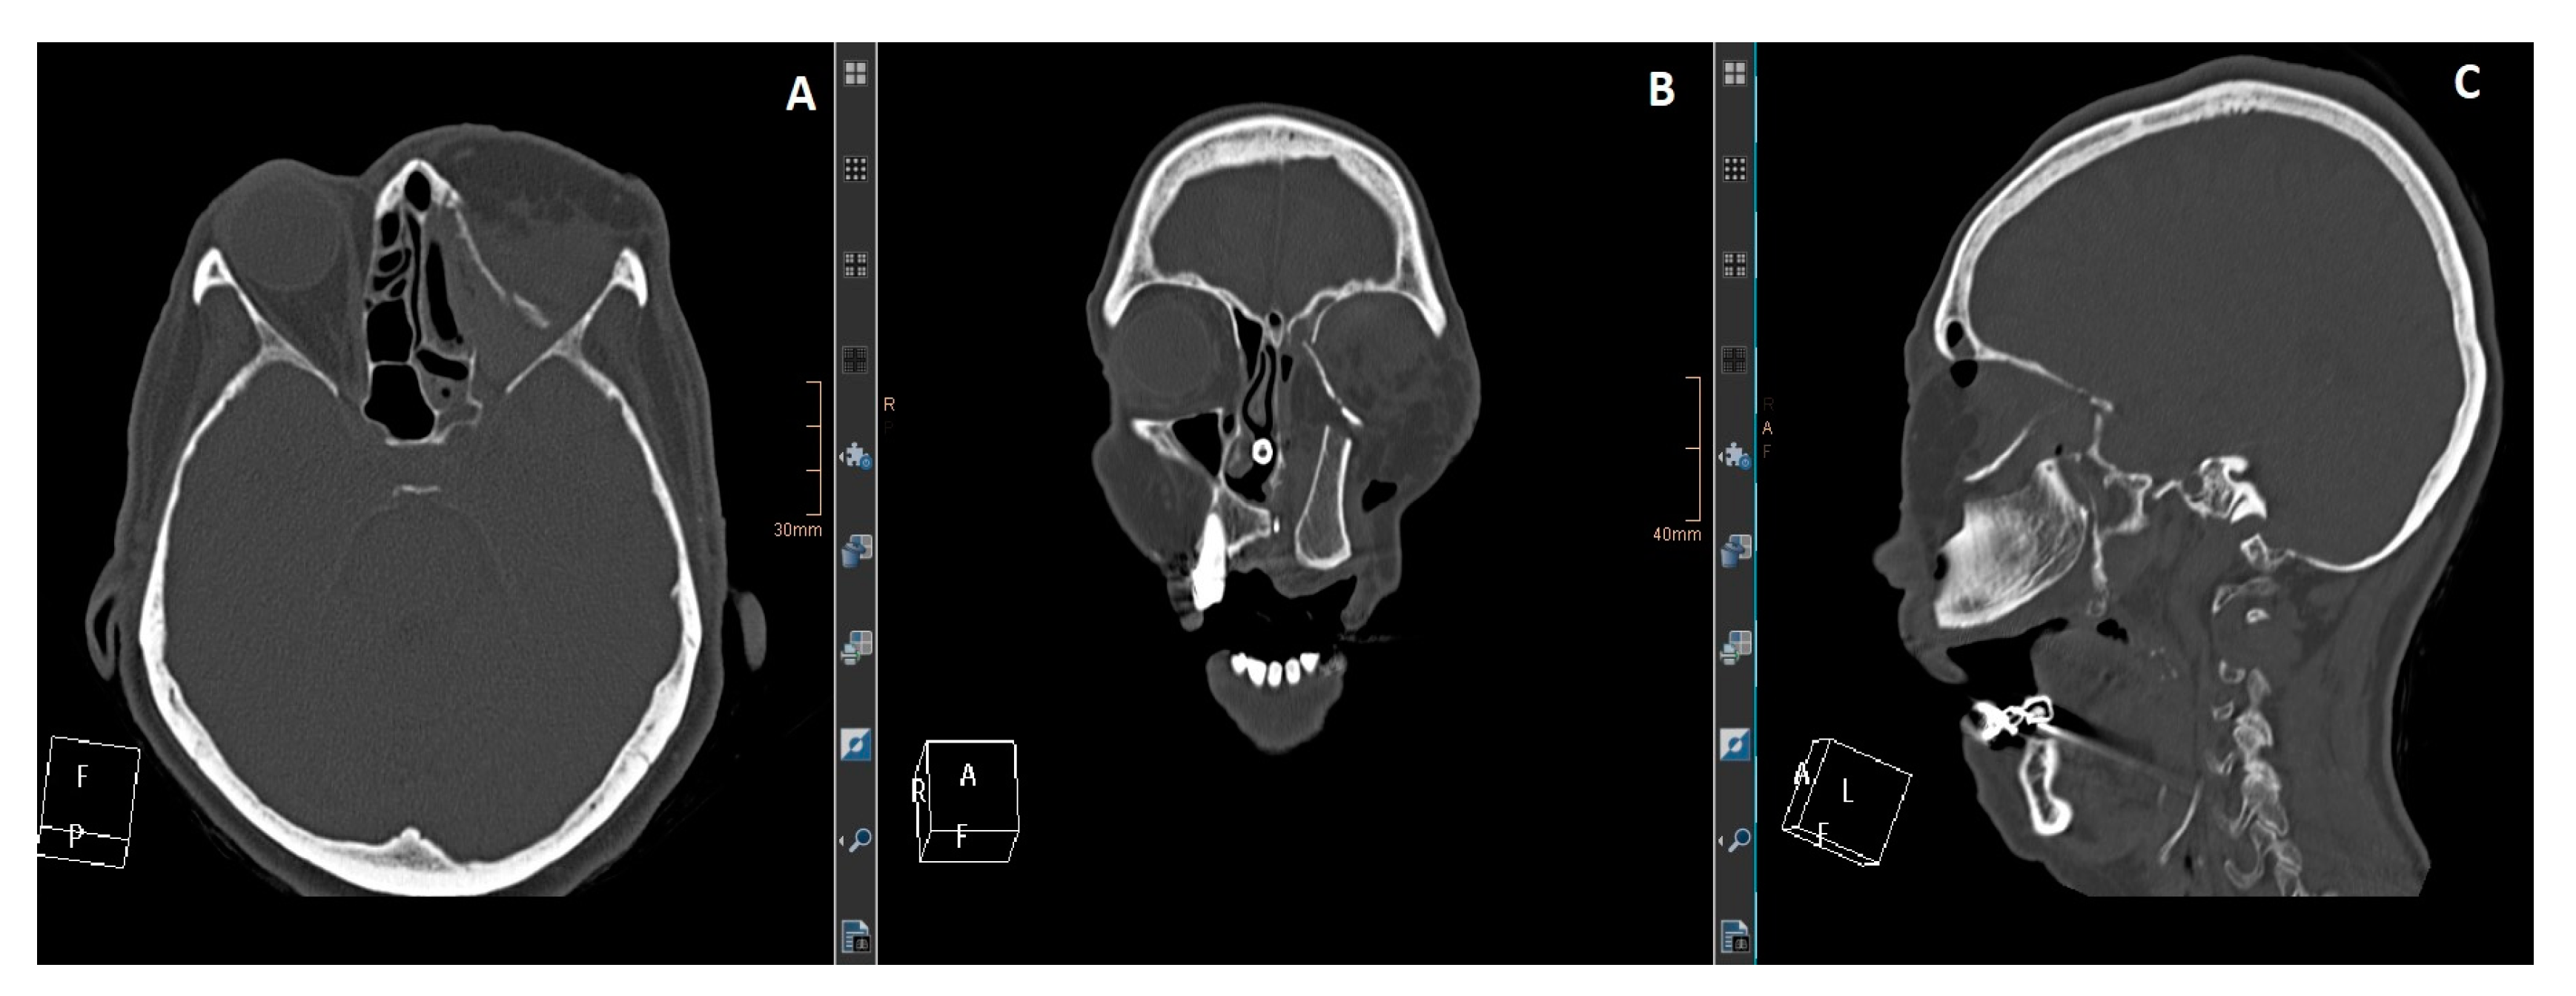

Here, support and volume are required to obtain an aesthetically pleasing and functional reconstruction. A DCIA with internal oblique muscle and skin in conjunction with an MFC (or a perforator flap) can satisfy the above requirements. The DCIA replaces the maxilla, while the MFC reconstructs the orbital walls, as seen in the patient below (Figure 1, Figure 2, Figure 3, Figure 4, Figure 5 and Figure 6).

Figure 2. (A): Axial view. (B): coronal view. (C): sagittal view. CT imaging shows the maxilla reconstruction with a DCIA flap and the medial orbital wall and floor with an MFC flap. The reconstruction was delayed for two weeks after the resection to wait for definitive histology.